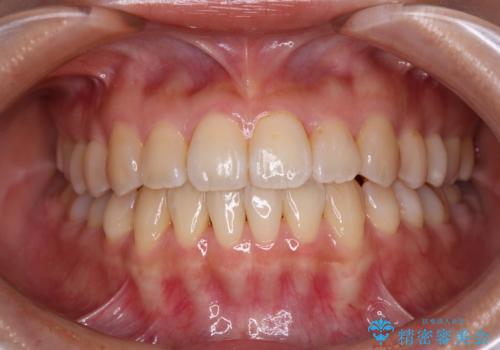

ワイヤー矯正で確実にガタつきを治したい セラミックブラケットによる治療